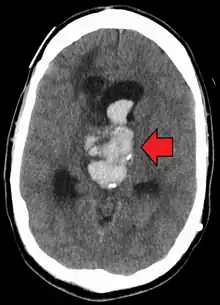

| Axiali CT scan of a spontaneous intracranial hemorrhage | |

CT scan (computed tomography) of the brain (without any iodinated contrast), is the initial imaging choice because of its high speed, good accessibility in hospitals, high sensitivity in detecting brain injuries or brain diseases, thus helping to triage patients in emergency department in a timely manner and urgent neurosurgical intervention can be administered. Examples of brain diseases that require urgent intervention are: large volume hemorrhage, brain herniation, and cerebral infarction. Other advantages of CT over MRI scan are ability to detect bony fractures, vascular injury, and cerebrospinal fluid (CSF) leak. It also does not need to screen for MRI safety of implants/foreign body especially for penetrating or blast injuries.[4] Moreover, CT scans have also been used to train deep learning models to automatically perform intracranial hemorrhage detection.[5] Deep learning models have been found to reach expert-level performance.[6][7]